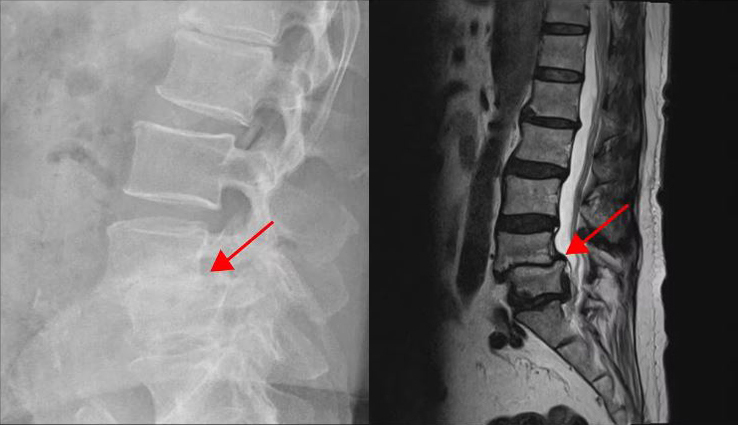

척추관이 심하게 좁아져서 실제 이 좁아진 척추관을 넓혀주지 않으면 증상이 전혀 개선되지 않을 것 같은 환자도 근육재활치료를 받으면 증상이 좋아지는 걸 볼 수 있습니다. 만약 협착증이 신경이 눌리는 것 때문에만 발생하는 병이라면, 척추관이 심하게 막힌 중증 협착증 환자들은 어떠한 비수술치료를 받아도 증상이 좋아지지 않아야 정상입니다. 그런데 척추관이 심하게 막힌 사람들도 근육의 기능을 회복시키는 재활치료를 받고 증상이 많이 호전된다면 과연 이걸 무엇으로 설명할 수 있을까요?

그런데 만약 이 환자분들이 오로지 신경이 눌린 것 때문에만 아픈 것이었다면, 어떠한 비수술적 치료를 받아도 증상이 개선되지 않아야 정상입니다. 그런데 만일 이 환자분들이 근육재활치료를 통해 증상이 90% 이상 좋아진다면, 또 마비가 풀리고 통증이 완전히 사라진다면 어떨까요? 좁아진 척추관이나 추간공을 전혀 넓혀주지 않았는데 어떻게 증상이 개선될 수 있을까요? 이 환자분들이 저희 병원에서 협착증 치료를 받은 후 어떤 결과가 나왔는지 아래에서 치료후기 영상을 꼭 보시길 바랍니다.